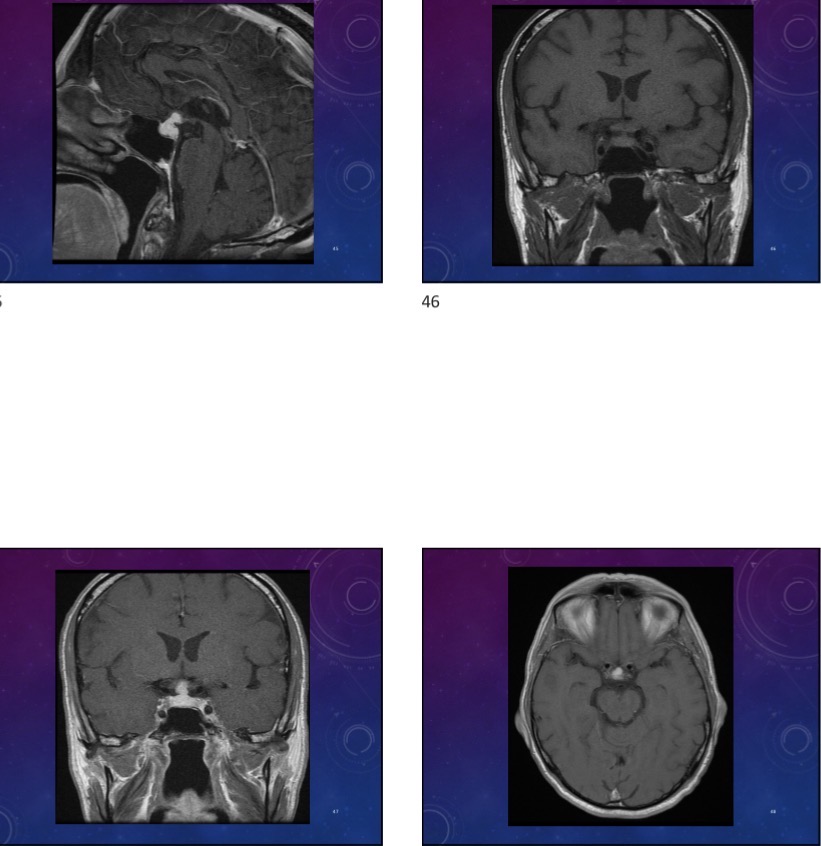

65-year-old male has a past history of CLL and is in remission is currently unwell and has a visual changes

Panpituitary lymphocytic hypophysitis bc of CLL.

Reactive chronic t lymphocytic infiltrate and fibrosis

Moderately thickened and lobulated stalk, superior extension to the hypothalamus. Pituitary gland and stalk are replaced by vividly homogenous enhancing tissue.